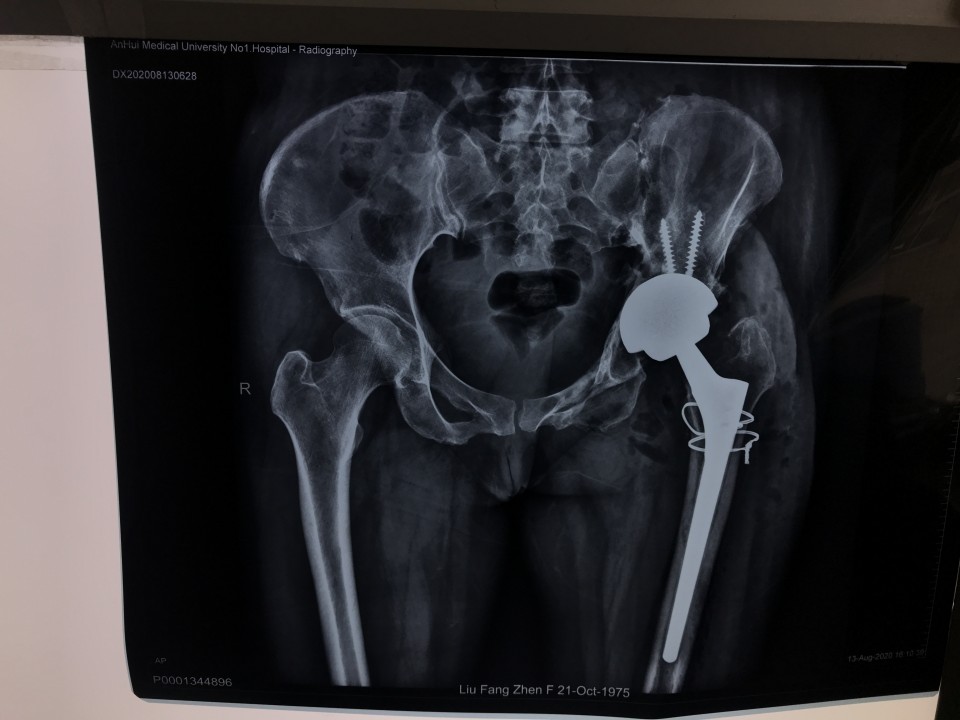

一位44岁女性患者因“左侧骨盆骨折术后疼痛伴渗液8年”入院。患者8年前因左侧骨盆骨折请上海专家行手术治疗,术后恢复不佳,髋关节感染,当地医生将部分钢板取出,残留的钢板因风险极大未予以处理。由于手术不彻底,伤口继续流脓,股骨头坏死,关节疼痛严重。因为手术风险极大,失败率高,多家医院拒收,患者慕名来到我院关节与显微修复外科胡孔足主任专家门诊,胡主任综合考虑各方因素以及现阶段我院的诊疗技术,将患者收治入院予以手术。术前结合患者病史,体检及辅助检查,反复讨论,制定了精细的手术方案,于6月10日,成功行一期手术,取出感染发炎的钢板,植入抗生素占位器。因为钢板和血管神经紧紧粘连在一起,稍有不注意就可能导致大出血,瘫痪、心跳骤停等严重后果。术后培养提示为MRSA,经过两个月规范抗感染治疗,培养提示阴性,未见细菌,感染消失。8月12日,胡主任顺利完成二期手术,“左侧全髋关节置换术”,目前手术后4天,患者已经能够扶拐下地行走,恢复良好,不久将康复出院。